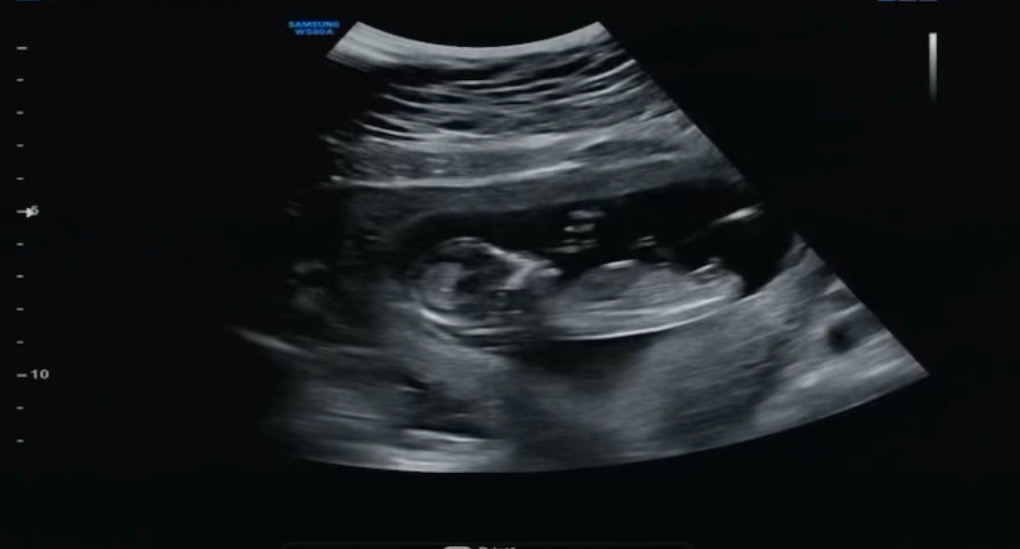

12주6일 각도법 투표부탁드려요